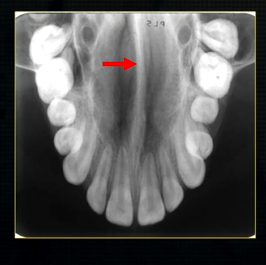

what does this anterior periapical graph show?

oval radiolucent area between the central incisors - is it Infront of the teeth (buccally?) or is it behind them? - you can’t tell radiographically

but its shape and position is compatible with the palatally positioned with the nasopalatine formaina

more posteriorly - radiopacities indicate the nasal septum and floor of the nose

dense, thin , white line in the middle of the image is the nasal septum

less dense opacity is caused by the

inferior nasal concha

radiolucency - nasal septum

lateral wall of the nose

maxillary air sinus

mid-palatal suture

this increased radiopacity is caused by the soft tissues at the tip of the nose - shadow - dense tissue